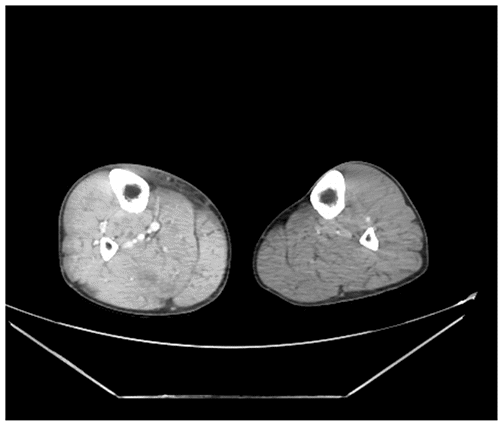

Imaging studies were performed to investigate the cause of his paralysis and right leg symptoms. A cervical spine CT scan was obtained to assess for potential fractures due to tenderness and paralysis. Additionally, a CT angiogram of his bilateral lower extremities was performed to evaluate for occult fractures or arterial injury contributing to suspected right calf compartment syndrome (Figure 1). The initial electrocardiogram (ECG) is shown in Figure 2.

Figure 1. Bilateral Lower Extremity CT Angiography. Published with Permission

Prompt intervention focused on stabilizing the cardiac membrane with intravenous calcium and shifting potassium intracellularly using insulin and glucose. Imaging (CT scans of the cervical spine and lower extremities) ruled out fractures or vascular injuries but identified hypoattenuating areas within the right calf muscle, suggestive of rhabdomyolysis involvement. Due to airway compromise and critical electrolyte imbalance, the patient underwent emergent intubation and dialysis in the surgical ICU.